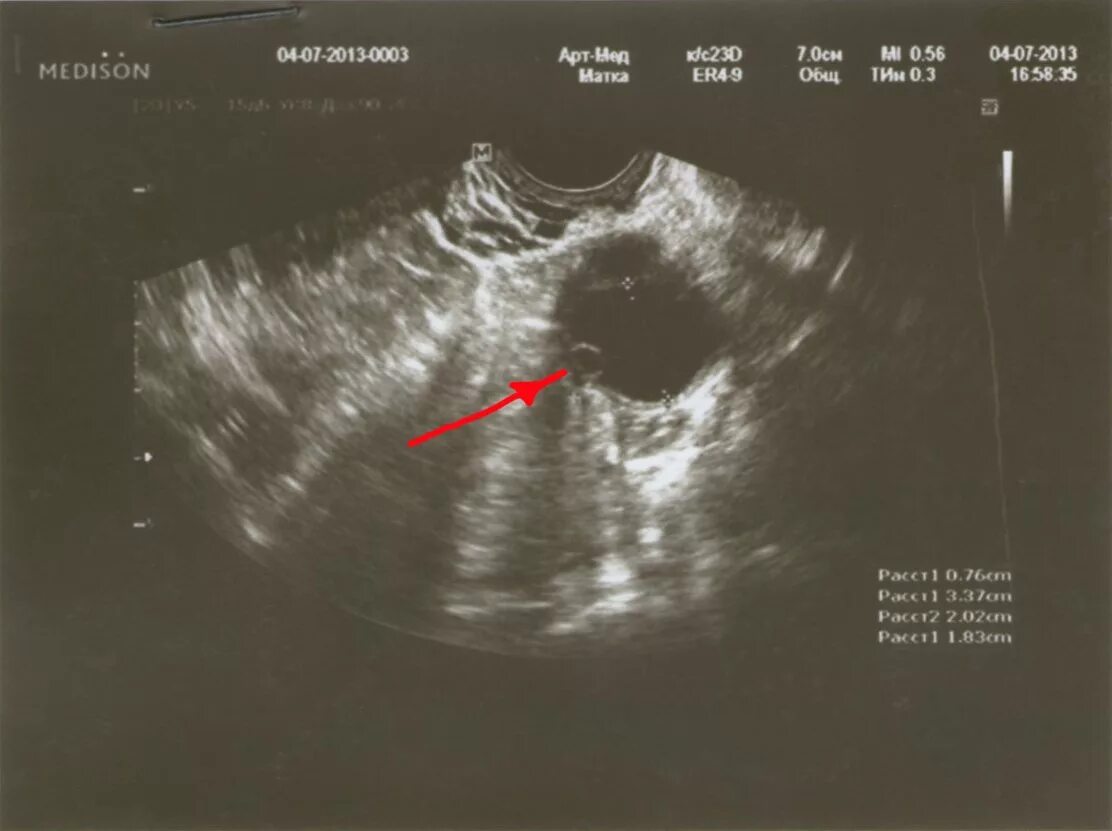

Фолликул 18 мм